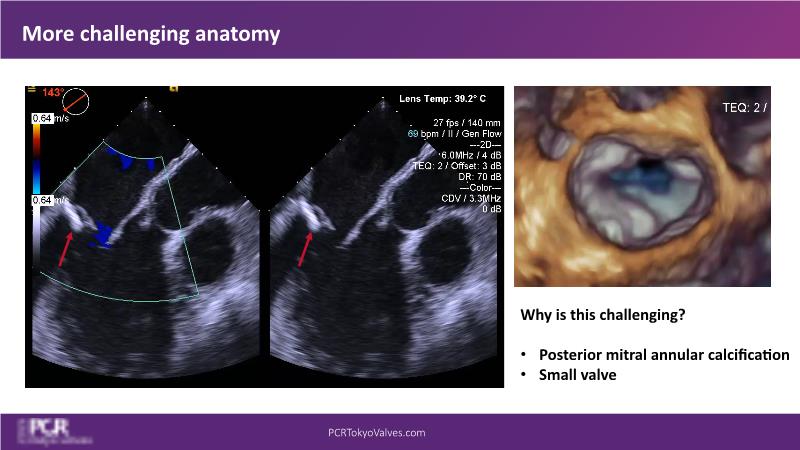

Watch this session to get an overview of a new TEER device, follow the step-by-step procedure related to initial experiences with this device for a Japanese patient with degenerative mitral regurgitation, learn about the latest data from RCT and registries, and follow discussions of challenging TEER cases!